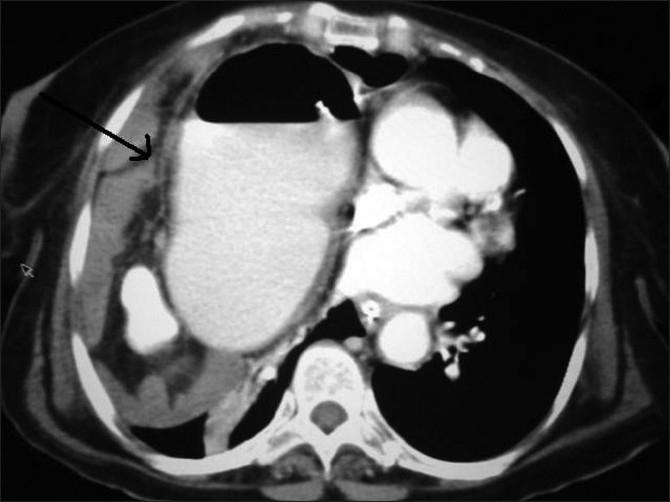

Hernia of Morgagni occurs through an anterior defect in the diaphragm. Symptoms of these hernias are attributable to the herniated viscera. In our case, there was partial obstruction due to herniation of the distal stomach and pylorus into the right hemithorax that was reduced surgically through a right thoracolapaorotomy. Of special emphasis are the various modalities used to diagnose this condition in our case.

莫尔加尼疝通过膈肌前部缺损形成。这些疝的症状归因于疝入的内脏。在我们的病例中,由于远端胃和幽门疝入右胸腔导致部分梗阻,通过右侧胸腹联合切口手术复位。特别强调的是在我们病例中用于诊断这种疾病的各种方法。